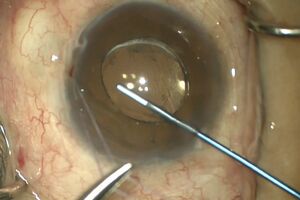

Placement of a temporal-beveled, self- sealing paracentesis during filtration surgery before the sclerotomy but after application/rinsing of an antifibrotic agent is essential in allowing the surgeon access to the anterior chamber, similar to cataract surgery (Figure 4-5). A paracentesis enables the surgeon to allow for gradual pressure decline in patients in whom the IOP is high (reducing the risk of suprachoroidal hemorrhage), and to reform the anterior chamber to assess for adequate filtration at the flap margins after sclera flat closure.